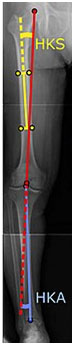

To indicate knee replacement in case of osteoarthritis, its radiographic classification and severity of symptoms should both be substantial. Such radiography should consist of weightbearing X-rays of both knees- AP, Lateral, and 30 degrees of flexion. AP and lateral views may not show joint space narrowing, but the 30 degree flexion view is most sensitive for narrowing. Full length projections are also used in order to adjust the prosthesis to provide a neutral angle for the distal lower extremity. Two angles used for this purpose are:

- Hip-knee-shaft angle (HKS), an angle formed between a line through the longitudinal axis of the femoral shaft and its mechanical axis, which is a line from the center of the femoral head to the intercondylar notch of the distal femur.

- Hip-knee-ankle angle (HKA), which is an angle between the femoral mechanical axis and the center of the ankle joint.

Angles commonly measured before knee replacement surgery:

- Hip-knee-shaft angle (HKS)

- Hip-knee-ankle angle (HKA)